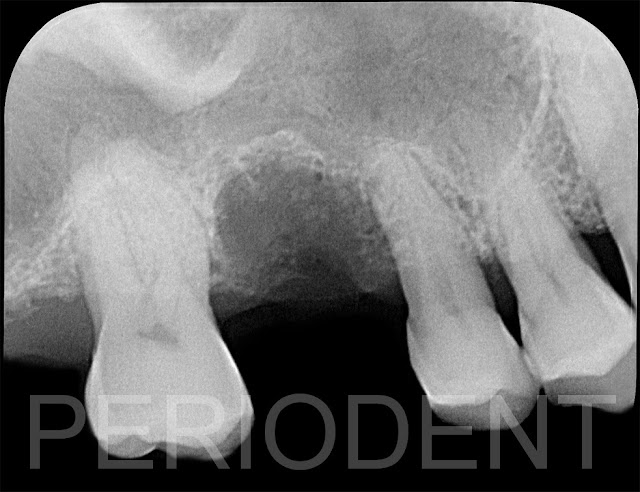

患者右上第一大臼齒顎側牙周發炎,經X光檢查,可見深度囊袋

先拔除第一大臼齒

患者決定採用植牙治療,口內照根尖片及CT檢查結果